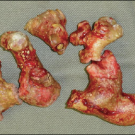

Ricky Kortyna, MMS, PA-C; Emily Murphy, MPAS, PA-C

A 36-year-old woman was seen in the emergency department secondary to the acute onset of right lower-quadrant pain.